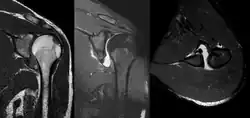

MRI of the shoulder after an anterior dislocation showing a Hill-Sachs lesion and labral Bankart lesion

MRI of the shoulder after an anterior dislocation showing a Hill-Sachs lesion and labral Bankart lesion